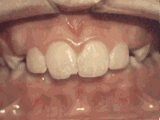

第四種

牙列擁擠,牙槽骨過窄,牙齒沒有足夠空間,只好前后左右高低上下亂長,經(jīng)過矯正后的牙齒是這樣的~